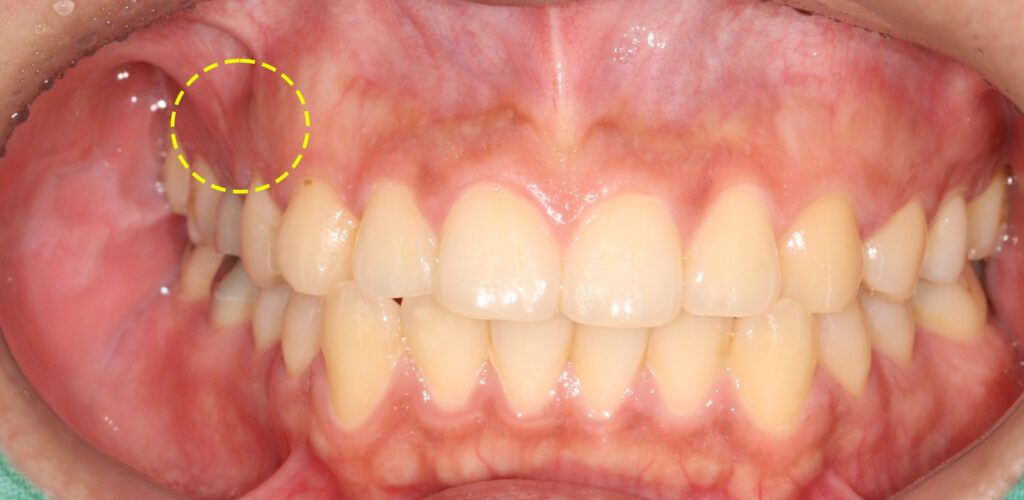

치료를 완료한 후의 모습입니다.

얼굴의 부종 감소와 눌렀을 때의

통증이 소실된 것을 확인한 뒤

최종 보철물을 시행하였습니다.

아직은 상처가 남아 있는 듯 보이는데요.